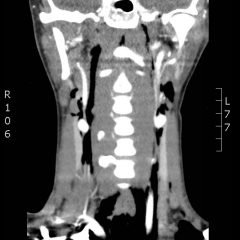

Oral ranula. On oral inspection he had a 3 x 1.5 cm, soft, non-tender, mobile, cystic, sublingual mass on the right aspect of the floor of his mouth that did not move with swallowing (Image 1). There was mild associated submandibular swelling on the right side of his face.